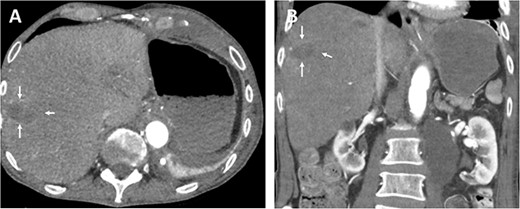

The postoperative recovery was uneventful. We achieved adequate pain control with patient-controlled intravenous analgesia. Inflammation and transaminases levels decreased, and symptoms significantly improved. Diuresis was adequate with normal renal parameters. We performed Partial Thromboplastin Time (PTT)-controlled anticoagulation with a target PTT of 50–60 seconds using intravenous heparin. The patient was transferred to the normal departure on the third postoperative day. Postoperative CT angiography demonstrate enhancement during contrast-enhanced phase and hepatic ischemic area with irregular margins (Fig. 3).

Postoperative axial (A) and coronal (B) CT angiographic images demonstrate enhancement during contrast-enhanced phase and hepatic ischemic area with irregular margins. (C) 3D reconstructed CT angiography shows antegrade visceral reconstruction with a bifurcated graft from the supra-celiac aortic donor to the superior mesenteric and celiac arteries (arrows).